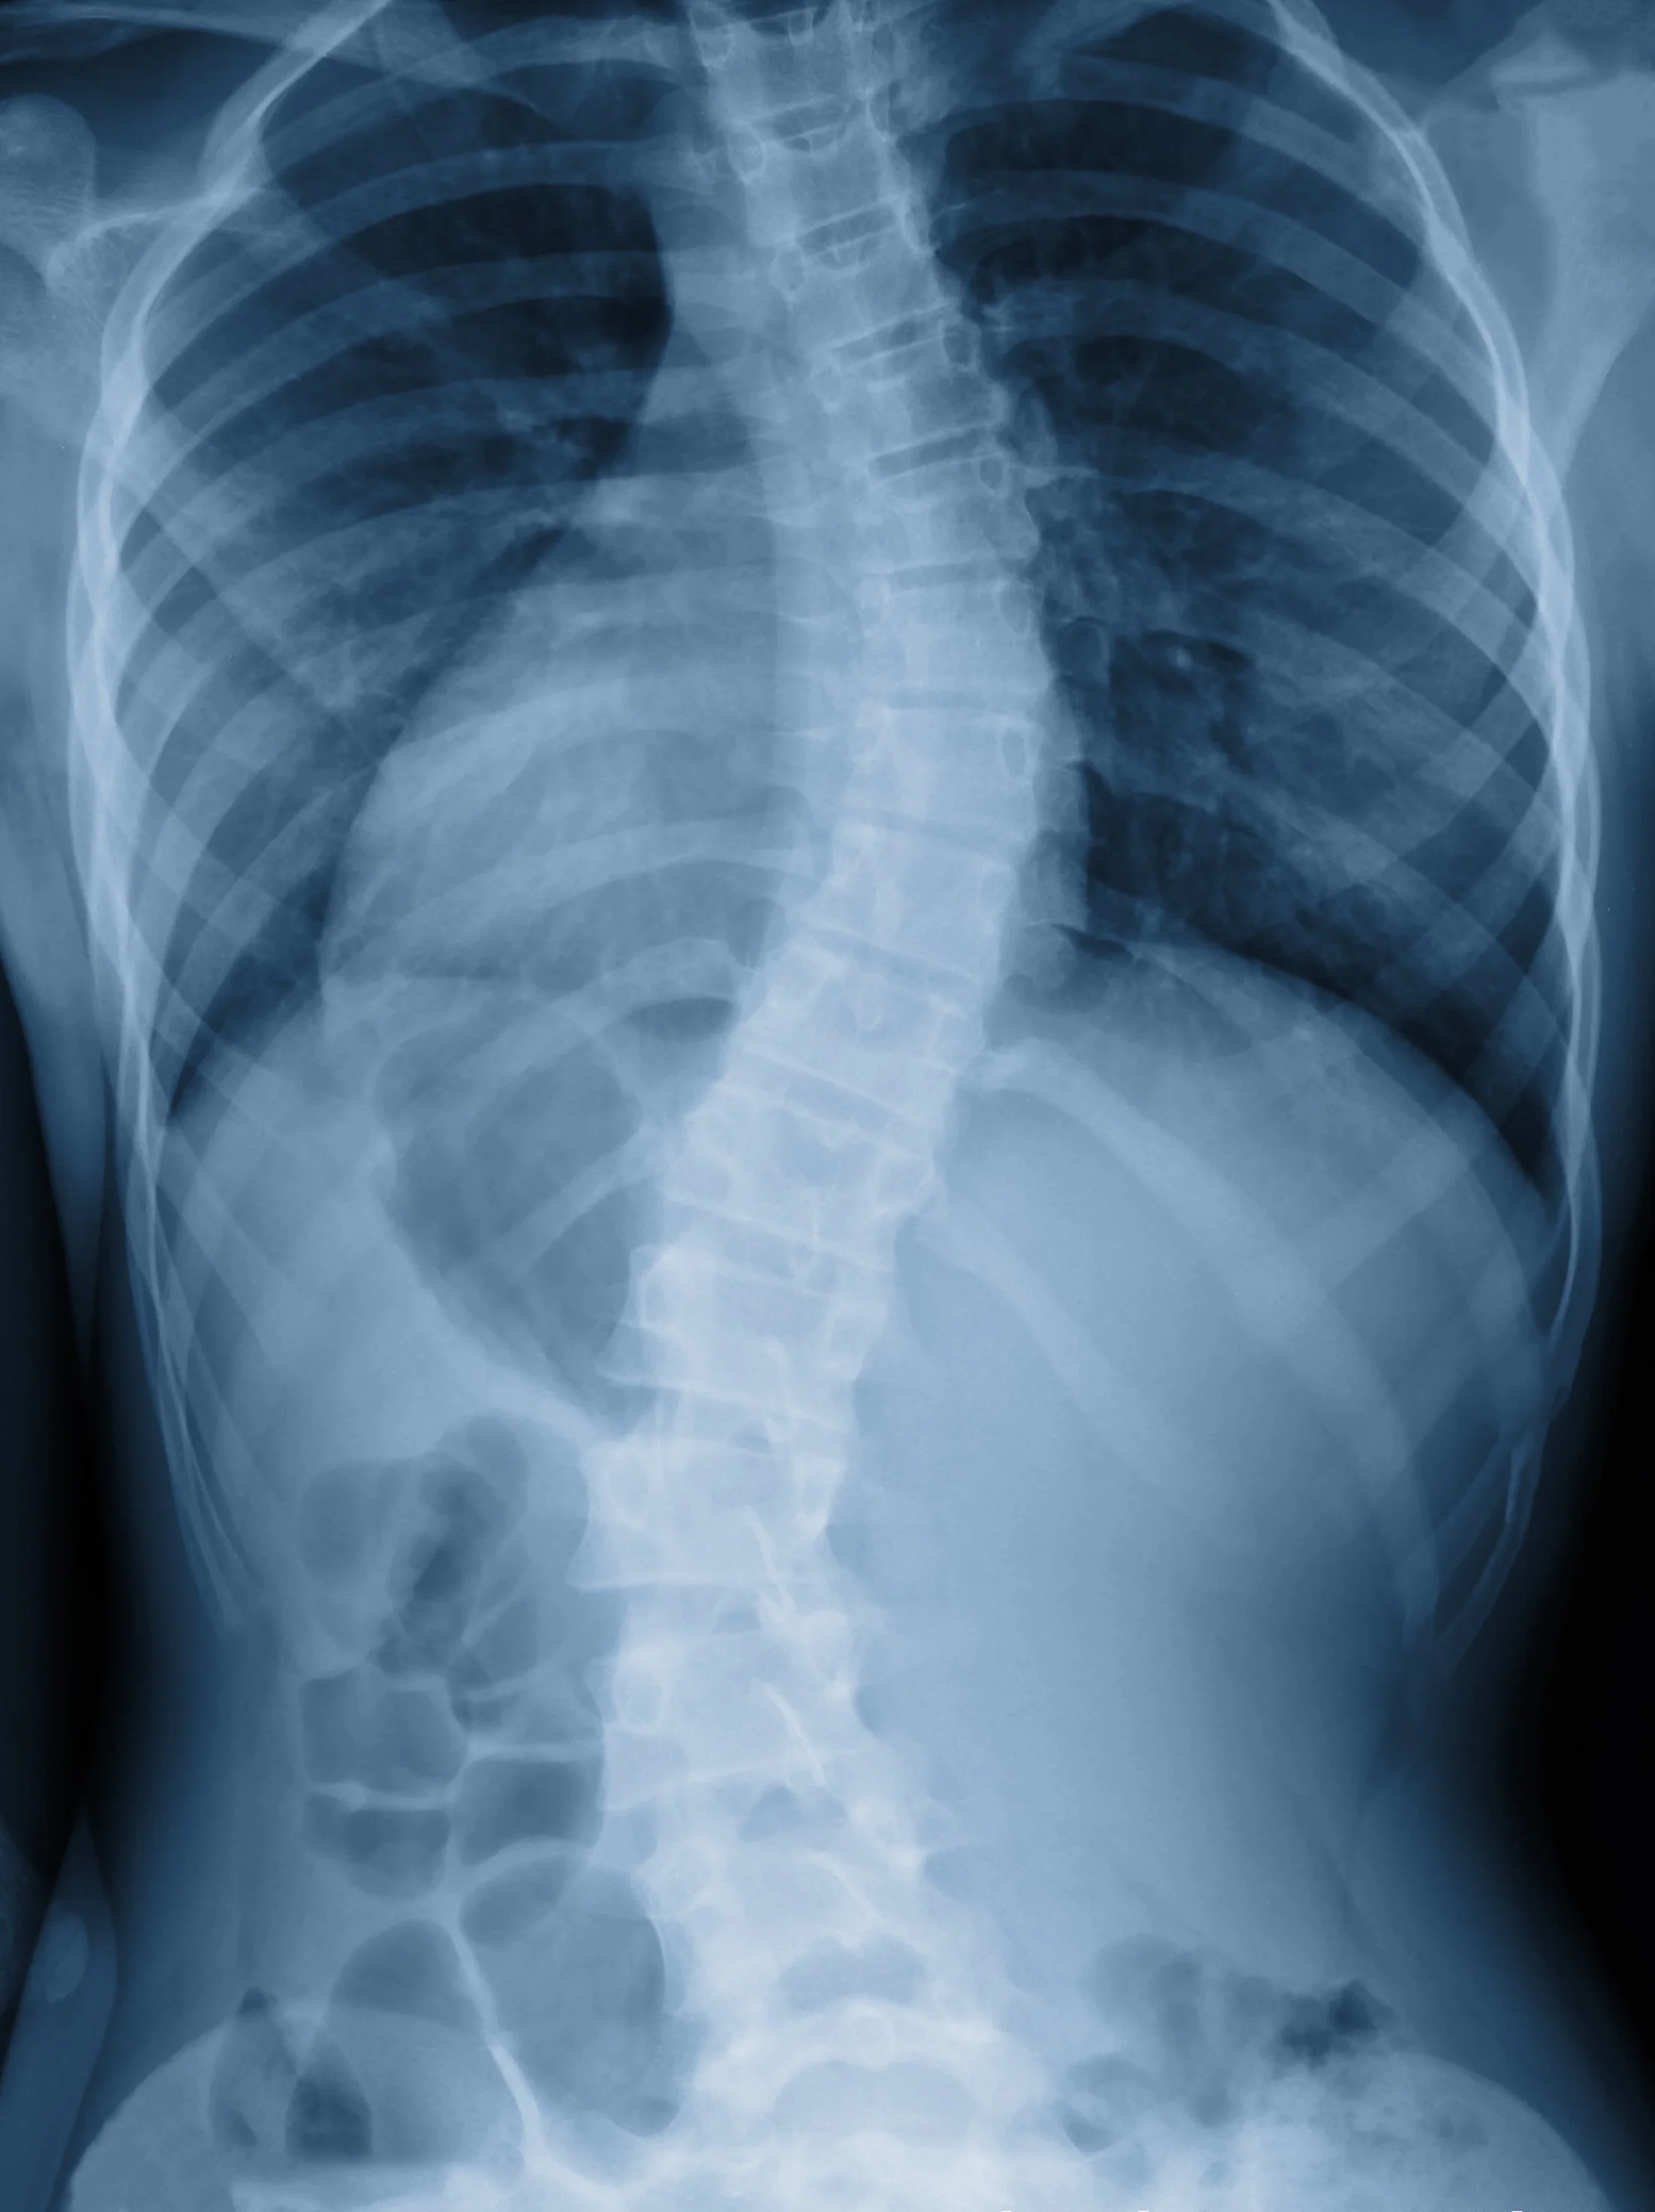

Scoliosis is a condition where the spine curves sideways, often leading to muscular imbalance, joint stress, and discomfort. Pain from scoliosis can develop at any age and is usually caused by uneven load distribution, postural strain, or compensatory muscle tension. Physiotherapy can reduce pain, restore movement, and strengthen the muscles supporting the spine to improve daily function and quality of life.

Scoliosis